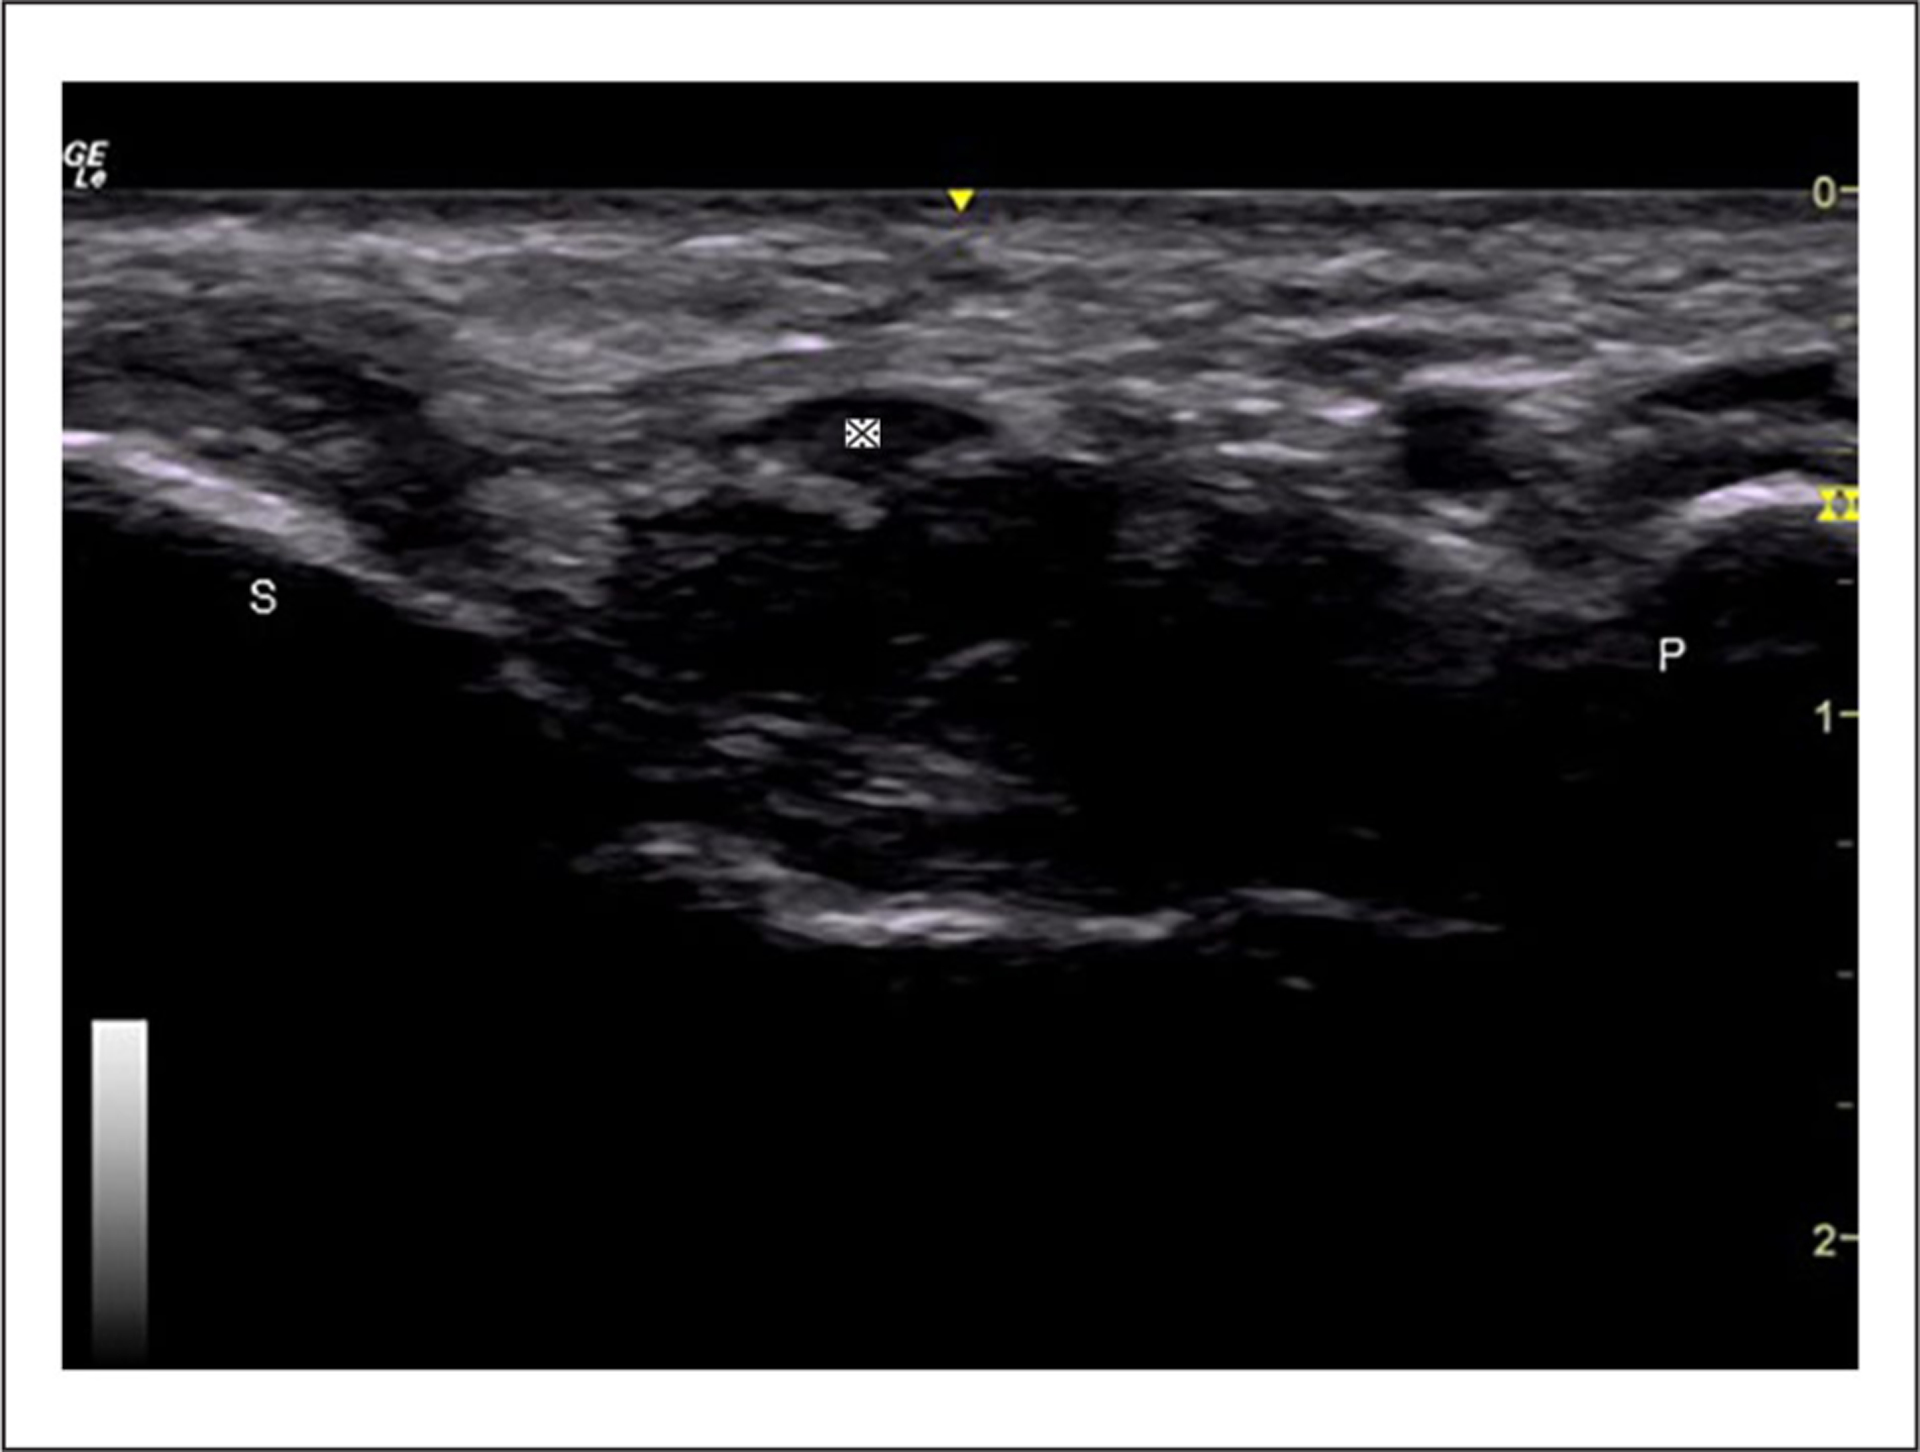

This study examined the implementation of a Doppler sonography imaging protocol to assess intraneural blood flow, within the median nerve, in healthy individuals.

A large percentage of missing evidence (11%–35%) across proximal, mid, and distal carpal tunnel locations. Only a quarter of cases with evidence of intraneural blood flow had the strongest evidence of a power Doppler video clip, of which only three-quarters were valid. The study identified potential areas for improving the imaging protocol to reduce missing data and improve data quality.

This study demonstrates the significance of a standardized imaging protocol to guide the sonographic acquisition of Doppler images and provides important insights into potential issues with data quality. The recommendations have the potential to help future studies assess intraneural blood flow in healthy populations in a more rigorous and reliable way. Incorporating the study’s recommendations into a standardized protocol, there is potential to enhance the diagnostic accuracy of carpal tunnel syndrome and improve diagnosis and treatment.